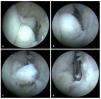

Fig. 14 La artroscopia en el compartimento posterior se inicia con la realización del abordaje dorsorradial y del abordaje transtendinoso desde el cual se introducirán los instrumentos (Figs. 6c). En el ángulo visual de la cámara por encima del portal posteroradial se encuentran la punta del olécranon y la fosa olecraniana. a) Con frecuencia existen adherencias masivas en la zona de la fosa olecraniana, que se separan con un resector sinovial y se extraen. b) En los casos con graves limitaciones de movimiento se puede realizar también una cirugía de la fosa con una fresa para hueso (no se representa en la imagen). Mediante esta cirugía se extraen las formaciones óseas molestas, así como formaciones osteofíticas en la zona de la fosa olecraniana, hasta que se restituye la libre movilidad entre el olécranon y la fosa olecraniana.

Fig. 15 a) Las formaciones osteofíticas en la zona del olécranon se extraen mediante un pequeño cincel Lambotte (5-6 mm) a través del portal transtendinoso. b) Después de haber desprendido los osteofitos, estos se extraen con una pinza de agarre. Para que la unión sea suave, se puede alisar la zona con un resector sinovial. Para finalizar, se verificará y documentará el rango de movimiento, se introducirá un drenaje de Redon en la articulación y se cerrarán los abordajes mediante una sutura de punto simple.

Fig. 16 Para la documentación de los resultados de la intervención quirúrgica se realiza un control radiológico en dos planos del codo antes del alta del paciente. a, b) Se pudieron extraer los osteofitos humerales presentes en el preoperatorio (flechas).